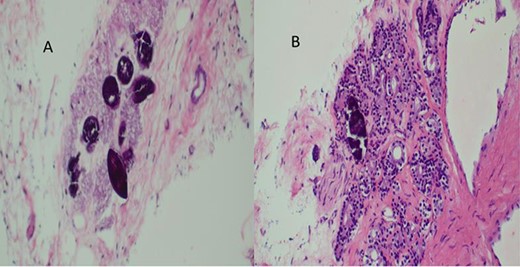

The report revealed a segment of colon with low-grade invasive adenocarcinoma (pT3NxM1) and Schistosoma eggs embedded in the tumor (Fig. 3).

(A) Histopathology of colon with adenocarcinoma associated with Schistosoma ova with poorly formed granulomatous inflammation, hematoxylin and eosin (H&E) ×20 magnification. (B) Adenocarcinoma and Schistosoma ova with dense lymphocytic infiltrates ×40 magnification.